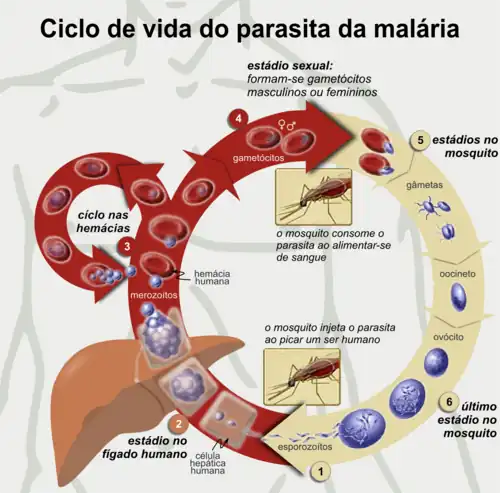

Ciclo de vida do parasita

No ciclo de vida do Plasmodium, a fêmea do mosquito Anopheles (o hospedeiro definitivo) transmite a um vertebrado (o hospedeiro secundário, como o ser humano) uma forma infecciosa móvel (denominada esporozoíto), atuando desta forma como vetor. O esporozoíto percorre os vasos sanguíneos até às células hepáticas, nas quais se reproduz assexualmente (através de esquizogonia tecidual), produzindo milhares de merozoítos. Estes últimos irão infectar mais glóbulos vermelhos e dar início a uma série de ciclos de multiplicação assexuada que produzem entre 8 a 24 novos merozoítos infecciosos cada um, até à célula romper e dar início a um novo ciclo de infecção.[27]

Os restantes merozoítos tornam-se gametócitos imaturos, os quais são os precursores dos gâmetas masculinos e femininos. Quando um mosquito pica uma pessoa infectada, os gametócitos são transportados no sangue e amadurecem no sistema digestivo do mosquito. Os gametócitos macho e fêmea fundem-se e formam um oocineto – um zigoto fertilizado móvel. Por sua vez, os oocinetos transformam-se em novos esporozoítos que migram para as glândulas salivares do insecto, prontos a infectar novos vertebrados. Quando o mosquito se alimenta através da picada, os esporozoítos são injectados para a pele através da sua saliva.[28]

Só a fêmea do mosquito é que se alimenta de sangue; os machos alimentam-se do néctar de plantas, pelo que não transmitem a doença. As fêmeas do género Anopheles preferem alimentar-se ao longo da noite, iniciando a procura de uma refeição com o pôr do sol.[29] Os parasitas da malária podem também ser transmitidos através de transfusões de sangue, embora a sua ocorrência seja rara.[30]

A infecção de malária desenvolve-se em duas fases: uma que envolve o fígado (fase exoeritrocítica) e outra que envolve os glóbulos vermelhos, ou eritrócitos (fase eritrocítica). Quando um mosquito infectado perfura a pele de uma pessoa para se alimentar de sangue, os esporozoítos presentes na saliva do mosquito penetram na corrente sanguínea e depositam-se no fígado, onde infectam os hepatócitos, reproduzindo-se assexualmente e sem haver manifestação de sintomas ao longo de 8-30 dias.[34]

Depois de um período de dormência no fígado, estes organismos diferenciam-se para produzir milhares de merozoítos, os quais, após romperem as células hospedeiras, se introduzem na corrente sanguínea e infectam os glóbulos vermelhos, dando início à fase eritrocítica do ciclo de vida.[34] O parasita é capaz de abandonar o fígado sem ser detectado, ao se envolver com a membrana celular da célula hepática do hospedeiro.[35] No interior dos glóbulos vermelhos, os parasitas reproduzem-se novamente, também de forma assexuada, rompendo periodicamente as células hospedeiras para infectar novos glóbulos vermelhos.[34]

Alguns esporozoítos P. vivax não se desenvolvem imediatamente em merozoítos, produzindo em vez disso hipnozoítos que permanecem adormecidos por intervalos de tempo que variam entre alguns meses, geralmente 7 a 10 meses, e vários anos. Após o período de hibernação, os hipnozoítos são reativados e produzem merozoítos. Os hipnozoítos são responsáveis pelos longos períodos de incubação e recidivas tardias em infecções por P. vivax,[32] embora se desconheça ainda a sua existência em casos de P. ovale.[36]

O parasita encontra-se relativamente protegido de ataques do sistema imunitário do corpo, uma vez que durante a maior parte do seu ciclo de vida humano se encontra no interior das células do fígado e dos glóbulos vermelhos, sendo por isso relativamente invisível à vigilância imunitária. No entanto, os glóbulos vermelhos infectados em circulação são destruídos no baço. Para evitar a sua destruição, o parasita P. falciparum introduz proteínas adesivas na superfície dos glóbulos vermelhos infectados, o que faz com que os glóbulos se agarrem às paredes dos vasos sanguíneos mais pequenos e não tenham que percorrer o sistema circulatório e passar pelo baço.[37] O bloqueio dos vasos pode provocar malária placentária.[38] Os glóbulos vermelhos sequestrados podem penetrar na barreira hematoencefálica e provocar malária cerebral.[39]